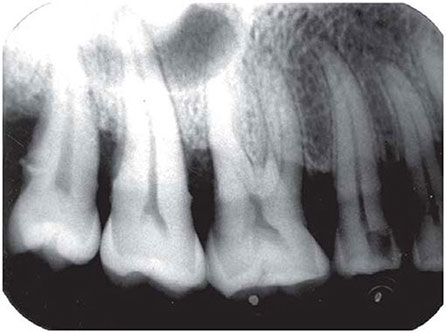

View Horizontal Bone Loss Periodontal Disease UK. Osteoporosis and tooth loss are health concerns that affect many older men and women. In periodontal disease, not only does the bone that supports the teeth, known as alveolar bone, reduce in height in relation to the teeth, but the morphology of the remaining alveolar bone is altered.

Atraumatic extraction of infected teeth. • horizontal bone loss • bone deformities (osseous defects) • vertical or angular • horizontal bone loss is the most common pattern of bone loss in periodontal disease. Horizontal bone loss is the most common pattern ol bone loss in periodontal disease. Horizontal ridge deficiency after extraction.